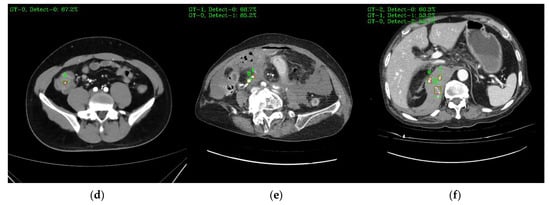

Figure 9 shows a visual representation of the results of lesion detection using the AH detector. Each image used for detection contains at least one GT-Box (green rectangle), which is the correct region. A P-Box (red rectangle), which is the detected region, is displayed according to the number of lesions detected and is not displayed when detection fails. The green text in the upper left corner of each image shows the index number of the GT-Box, index number of the detected P-box, and information about the IoU score. For example, Figure 9a shows that, for one GT-Box with a GT-Box index number of 0 (GT-0), two P-Box index numbers (Detect–{0, 1}) were generated with IoU scores of 76.8% and 42.8%. In addition, as shown in Figure 9c, out of the four GT-boxes with GT box index numbers GT–{0, 1, 2, 3}, only GT–{1, 3} was successfully detected, resulting in P-boxes with IoU scores of 69.8% and 79.6%, respectively.

Figure 9. Example images of the AH-lesion detected using the AH detector. Green boxes indicate GT-Box, and red boxes indicate P-Box. Green text is GT-Box index, P-Box index, and IoU score: (a) single GT-Box and detected two P-Box; (b) two GT-Box and detected each single and two P-Box; (c) four GT-Box: detected two P-Box and missed two P-Box; (d) single GT-Box: detected single P-Box; (e) two GT-Box: detected two P-Box; (f) three GT-Box: detected three P-Box.